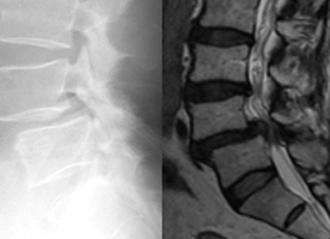

腰椎椎体間固定術(PLIF、TLIF、MIS-TLIF、KLIF、PETLIF)

通常の切開方法と低侵襲な切開方法があります。対象となる疾患は、腰椎椎間板ヘルニア、腰部脊柱管狭窄(症)、腰椎変性すべり症、腰椎変性側弯症、腰椎後弯症、腰椎分離(すべり)症の一部などです。近年、内視鏡や低侵襲手技を用いた椎体間固定術(MIS-TLIF、KLIF、PETLIFなど)が可能となっております。当院では、個々の病態によって術式を判断しております。原則、手術翌日より硬性のコルセットを装着し、起立・歩行を開始します。

第4腰椎に前屈時に増強するすべりを認め不安定性を示しています。 -

MIS-TLIF(低侵襲腰椎後方椎体間固定術) 椎間板にケージと言われるスペーサーが挿入され、また経皮的に椎弓根スクリューの挿入とロッドの連結がなされ、第4腰椎のすべりが矯正され固定されています。